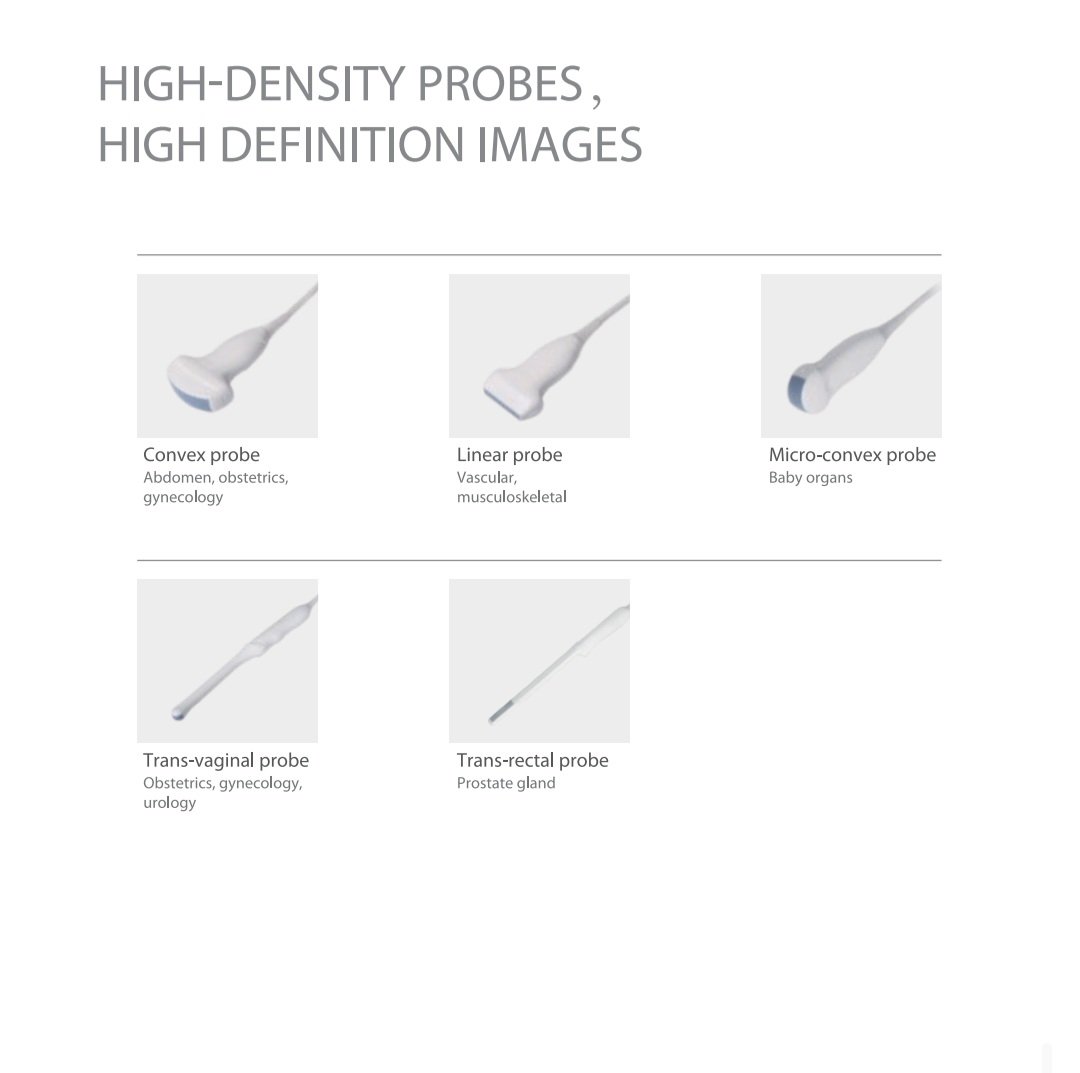

🩻 High-Density Probes for Superior Image Quality

This diagnostic ultrasound supports a range of high-density probes, each optimized for specific medical fields.

Available Probe Types:

-

Convex Probe: For abdomen, obstetrics, and gynecology applications.

-

Linear Probe: For vascular and musculoskeletal imaging.

-

Micro-convex Probe: Ideal for pediatrics and small organ imaging.

-

Transvaginal Probe: For gynecology, obstetrics, and urology examinations.

-

Transrectal Probe: For prostate and rectal imaging.

All probes deliver high-resolution, clear, and consistent images, ensuring diagnostic accuracy in every scan.